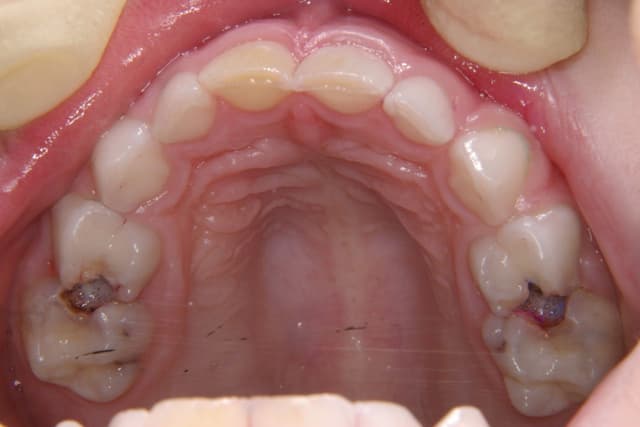

Chữa sâu răng số 7 là việc cần thiết khi răng hàm lớn này gặp phải các vấn đề sâu răng. Răng số 7 đóng vai trò quan trọng trong việc nghiền nát thức ăn hàng ngày, nhưng do nằm sâu trong cung hàm nên rất dễ bị sâu và khó vệ sinh kỹ. Điều […]